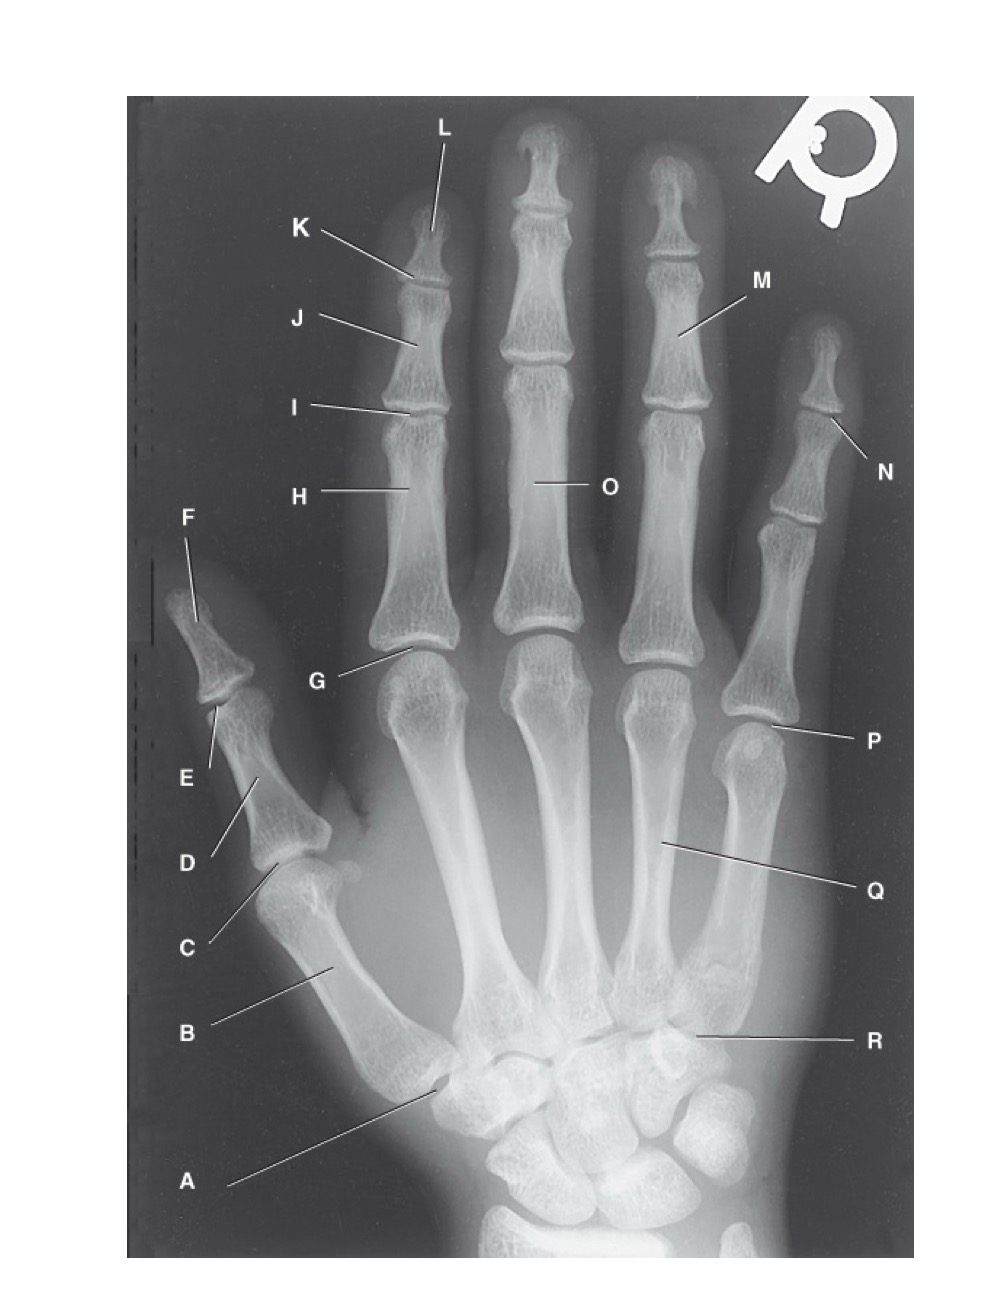

<p>identify A</p>

identify A

first carpometacarpal

14

New cards

<p>B?</p>

B?

first metacarpal

15

<p>C?</p>

C?

first metacarpophalangeal joint

16

<p>D?</p>

D?

proximal phalanx of the first digit

17

<p>E?</p>

E?

interphalangeal joint of the first digit

18

<p>F?</p>

F?

distal phalanx of the first digit

19

<p>G?</p>

G?

second metacarpophalangeal joint

20

<p>H?</p>

H?

proximal phalanx of the second digit

21

<p>I?</p>

I?

proximal interphalangeal joint of the second digit

22

<p>J?</p>

J?

middle phalanx of second digit

23

<p>K?</p>

K?

distal interphalangeal joint of second digit

24

<p>L?</p>

L?

distal phalanx of second digit

25

<p>M?</p>

M?

middle phalanx of the fourth digit

26

<p>N?</p>

N?

distal interphalangeal joint of fifth digit

27

<p>O?</p>

O?

proximal phalanx of third digit

28

<p>P?</p>

P?

fifth metacarpophalangeal joint

29

<p>Q?</p>

Q?

fourth metacarpal

30

<p>R?</p>

R?

fifth carpometacarpal joint